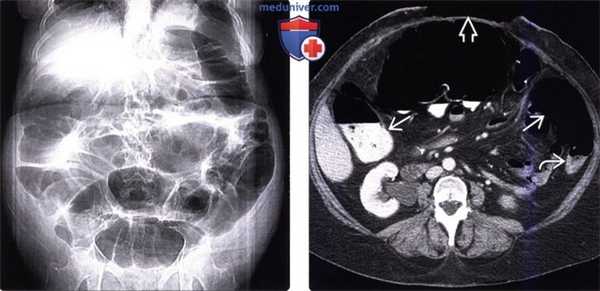

(Слева) На рентгенограмме в положении лежа на спине, выполненной женщине 63 лет, недавно перенесшей операцию по поводу вентральной грыжи, определяется диффузное расширение толстой кишки, при этом какого-либо расширения тонкой кишки не выявлено.

(Справа) На КТ у этой же пациентки визуализируется открытая рана после оперативного вмешательства по поводу грыжи. Толстая кишка диффузно расширена, в то время как тонкая кишка имеет нормальный поперечный размер. Расширение просвета толстой кишки сохраняется вплоть до прямой, хотя нисходящая ободочная кишка расширена в меньшей степени, что часто имеет место при илеусе, и не должно наводить на ошибочную мысль об обструкции.